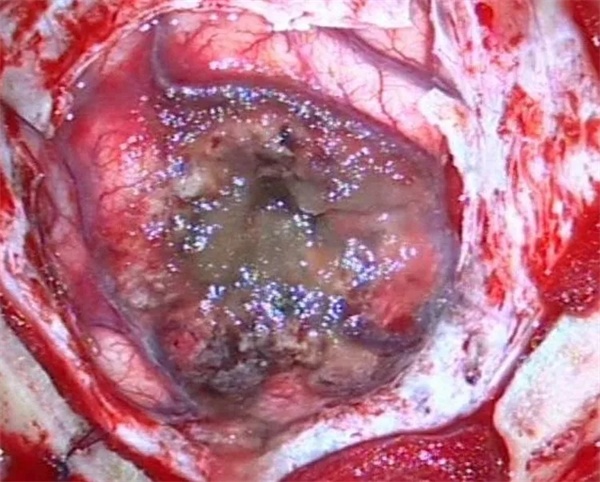

11月28日凌晨一点左右,朱某睡眠正酣,突发四肢抽搐,口吐白沫,双眼上翻,呼之不应,持续数分钟方才停止,睡在一旁的妻子目睹这一切,仿佛经历晴天霹雳,还以为丈夫“被鬼打了” 或“是中邪了”,一时间不知所措。待缓过神后还是拨打120,120把朱某送至捕鱼游戏 神经外科,头颅CT 检查提示右侧顶枕叶类圆形高密度占位,接诊医师姚勇、李世清考虑颅内占位所致继发性癫痫。